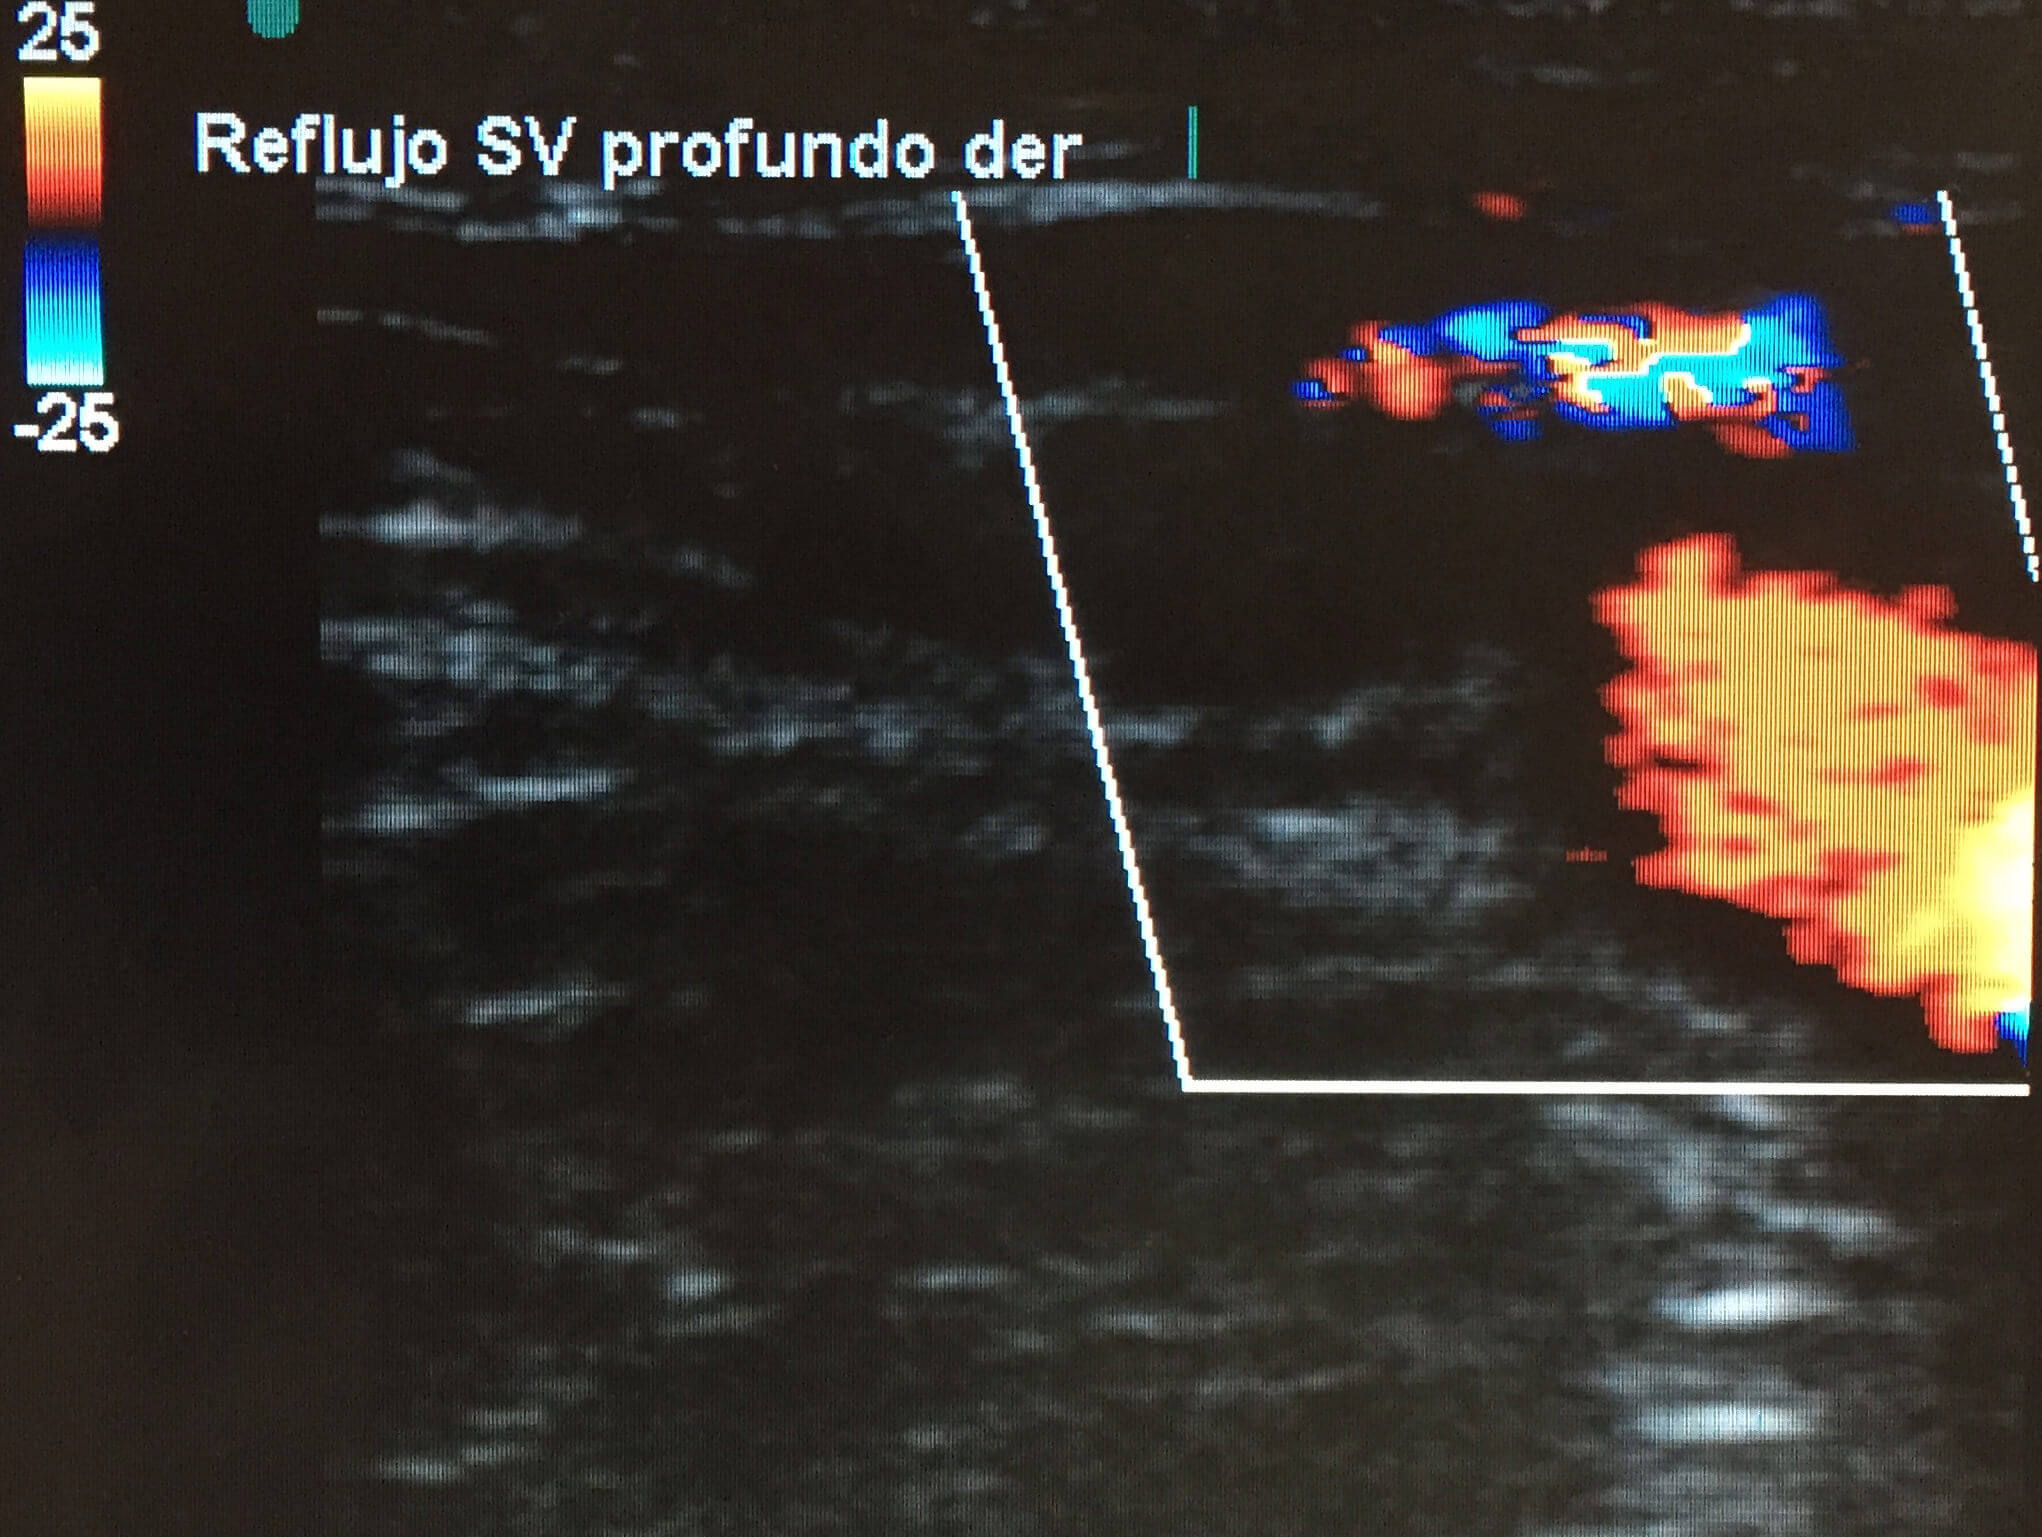

Se refiere al efecto Dúplex a que el médico quien realiza el estudio no sólo capta el espectro de ondas de flujo del Doppler sino que es capaz de visualizar la imagen bidimensional en tiempo real las diferentes estructuras anatómicas y en este caso las venas y las arterias.